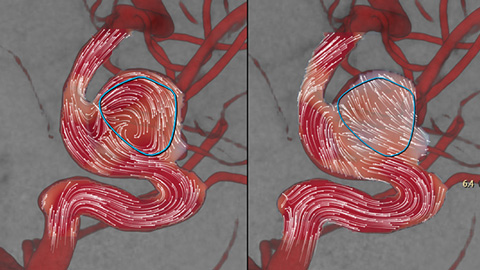

AneurysmFlow

Die funktionelle Beurteilung des Blutflusses nach abgeschlossener Intervention kann sich als schwierig erweisen. AneurysmFlow liefert Ihnen vor und nach dem Einsetzen eines Flow Diverters relevante Informationen. Durch Darstellung und Quantifizierung von Flussveränderungen sorgt es für größere Sicherheit im Hinblick auf den Eingriffserfolg.

Durch Visualisierung und Quantifizierung von Blutflussmustern im Ursprungsgefäß und Aneurysmasack werden wichtige Informationen gewonnen, die beim Einsetzen von Flow Divertern und anderen Embolisationsgeräten Unterstützung bieten können.

Nach der Aneurysmabehandlung werden die ordnungsgemäße Device-Positionierung und -Platzierung im Hinblick auf das Gefäß, den Aneurysmahals und den Aneurysmasack überprüft. AnerysmFlow ermöglicht die effiziente Messung der Wirksamkeit des eingesetzten Devices, sowie die Überprüfung auf mögliche arterielle Dissektionen, während sich der Patient noch auf dem Tisch befindet.

Sie können Veränderungen am Blutfluss im Aneurysma vor und nach der Behandlung durch Vergleich des Mittleren Aneurysma-Flussamplitudenverhältnisses (Mean Aneurysm Flow Amplitude Ratio, MAFA) vor und nach Einsetzen des Flow Diverters beurteilen.